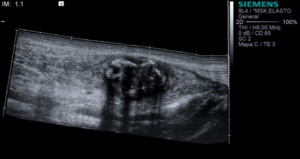

Eco Modo B